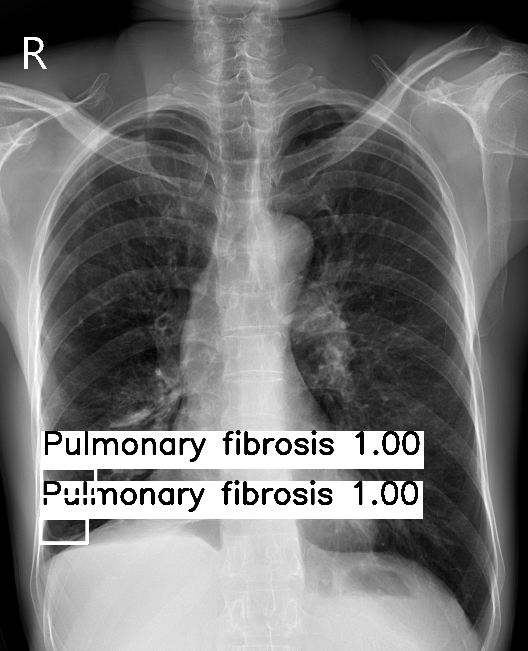

VinDR-CXR

Comparison of aggregated labels on the VinDR-CXR chest radiograph dataset. For WBF-EARL, the number beside the class label is the annotators' level of agreement while for Crowd R-CNN and BDC, the number indicates the class probability.

No Aggregation